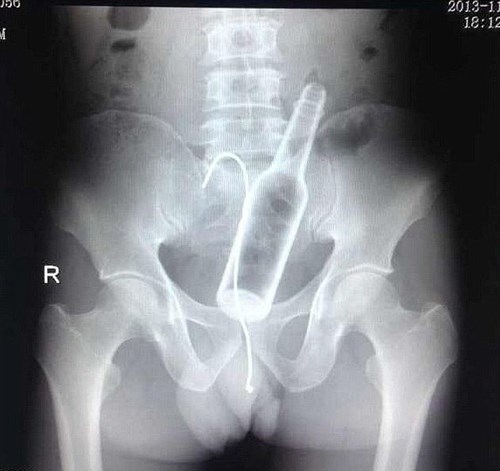

Việc phát hiện dị vật chủ yếu dựa trên quan sát. Trong một vài trường hợp phức tạp cần chụp X-quang để phát hiện dị vật.

Click vào ảnh để xem 4 hình ảnh minh họa